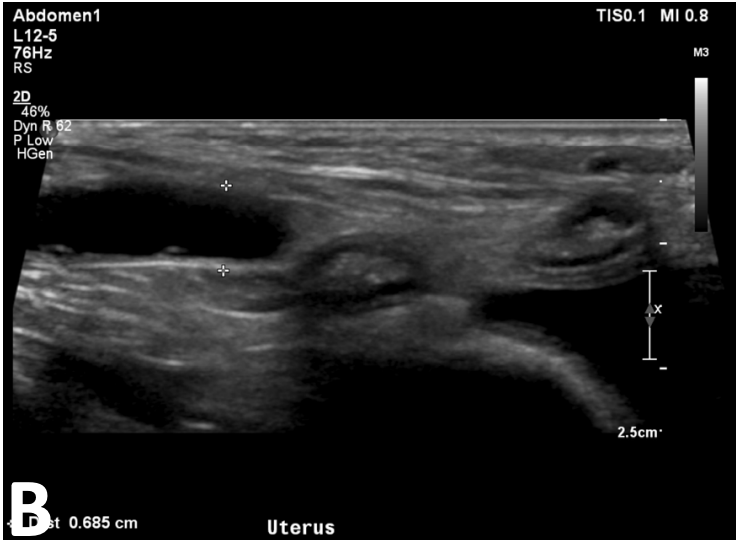

Q

What is shown in this image?

A

pyometra